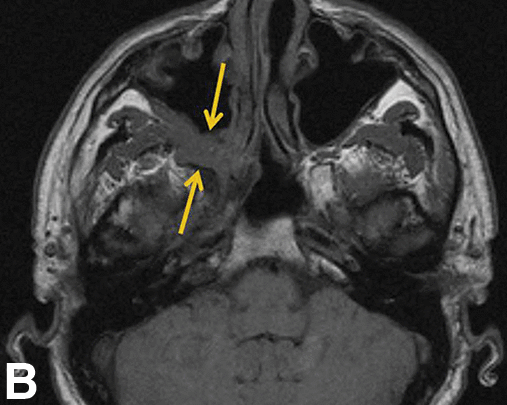

The orbital apex has fat. Tumor squeezing along cranial nerves through the superior and inferior orbital fissures and optic canal will blur this fat.

Melanoma on the right vs. normal on the left: